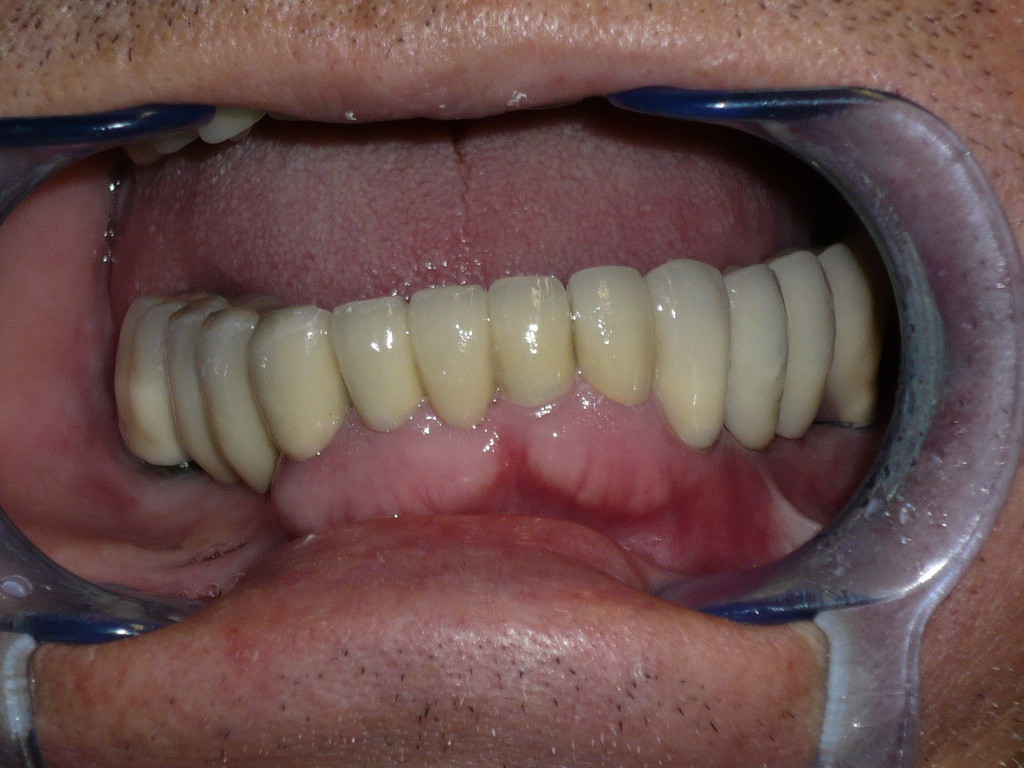

REHABILITACIÓN IMPLANTOSORTADA EN MANDÍBULA Y MAXILAR.

REHABILITACIÓN ESTÉTICA CON IMPLANTES.